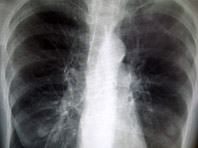

Университет Глазго нашел новый метод лечения астмы и ХОБЛа

Как передает Medical Express, речь идет о новом классе лекарств, которым удалось обратить вспять симптомы астмы у животных. Аналогичный эффект достигался и в экспериментах с образцами человеческих легких. Итак, новых подход опирается на активацию белка, реагирующего на жиры в рационе. Белок, называемый рецептором свободных жирных кислот 4 (FFA4), дислоцируется в кишечнике и поджелудочной железе, где…